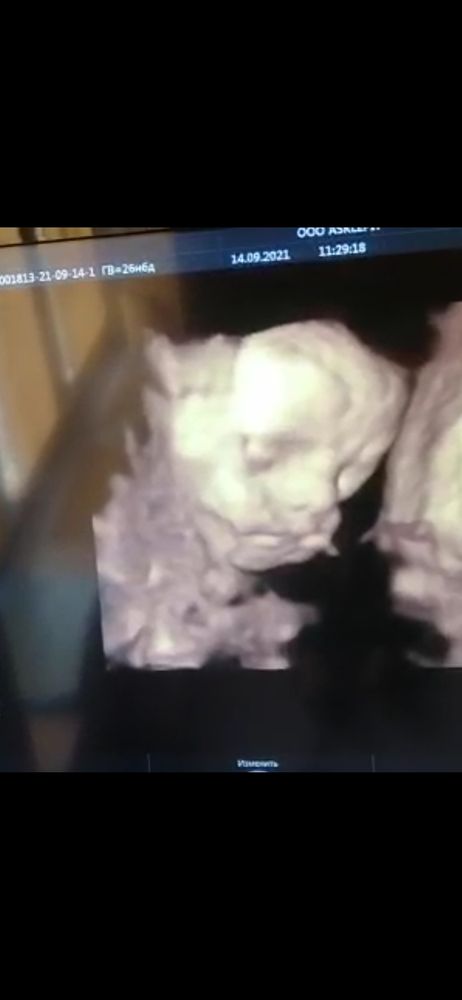

Вот такая папина мордашка) Ну, нос-точно)))))